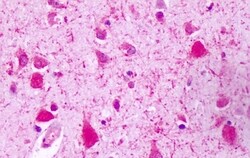

Invitrogen™ RAI3 Polyclonal Antibody

| Immunohistochemistry (Paraffin), Immunocytochemistry | |